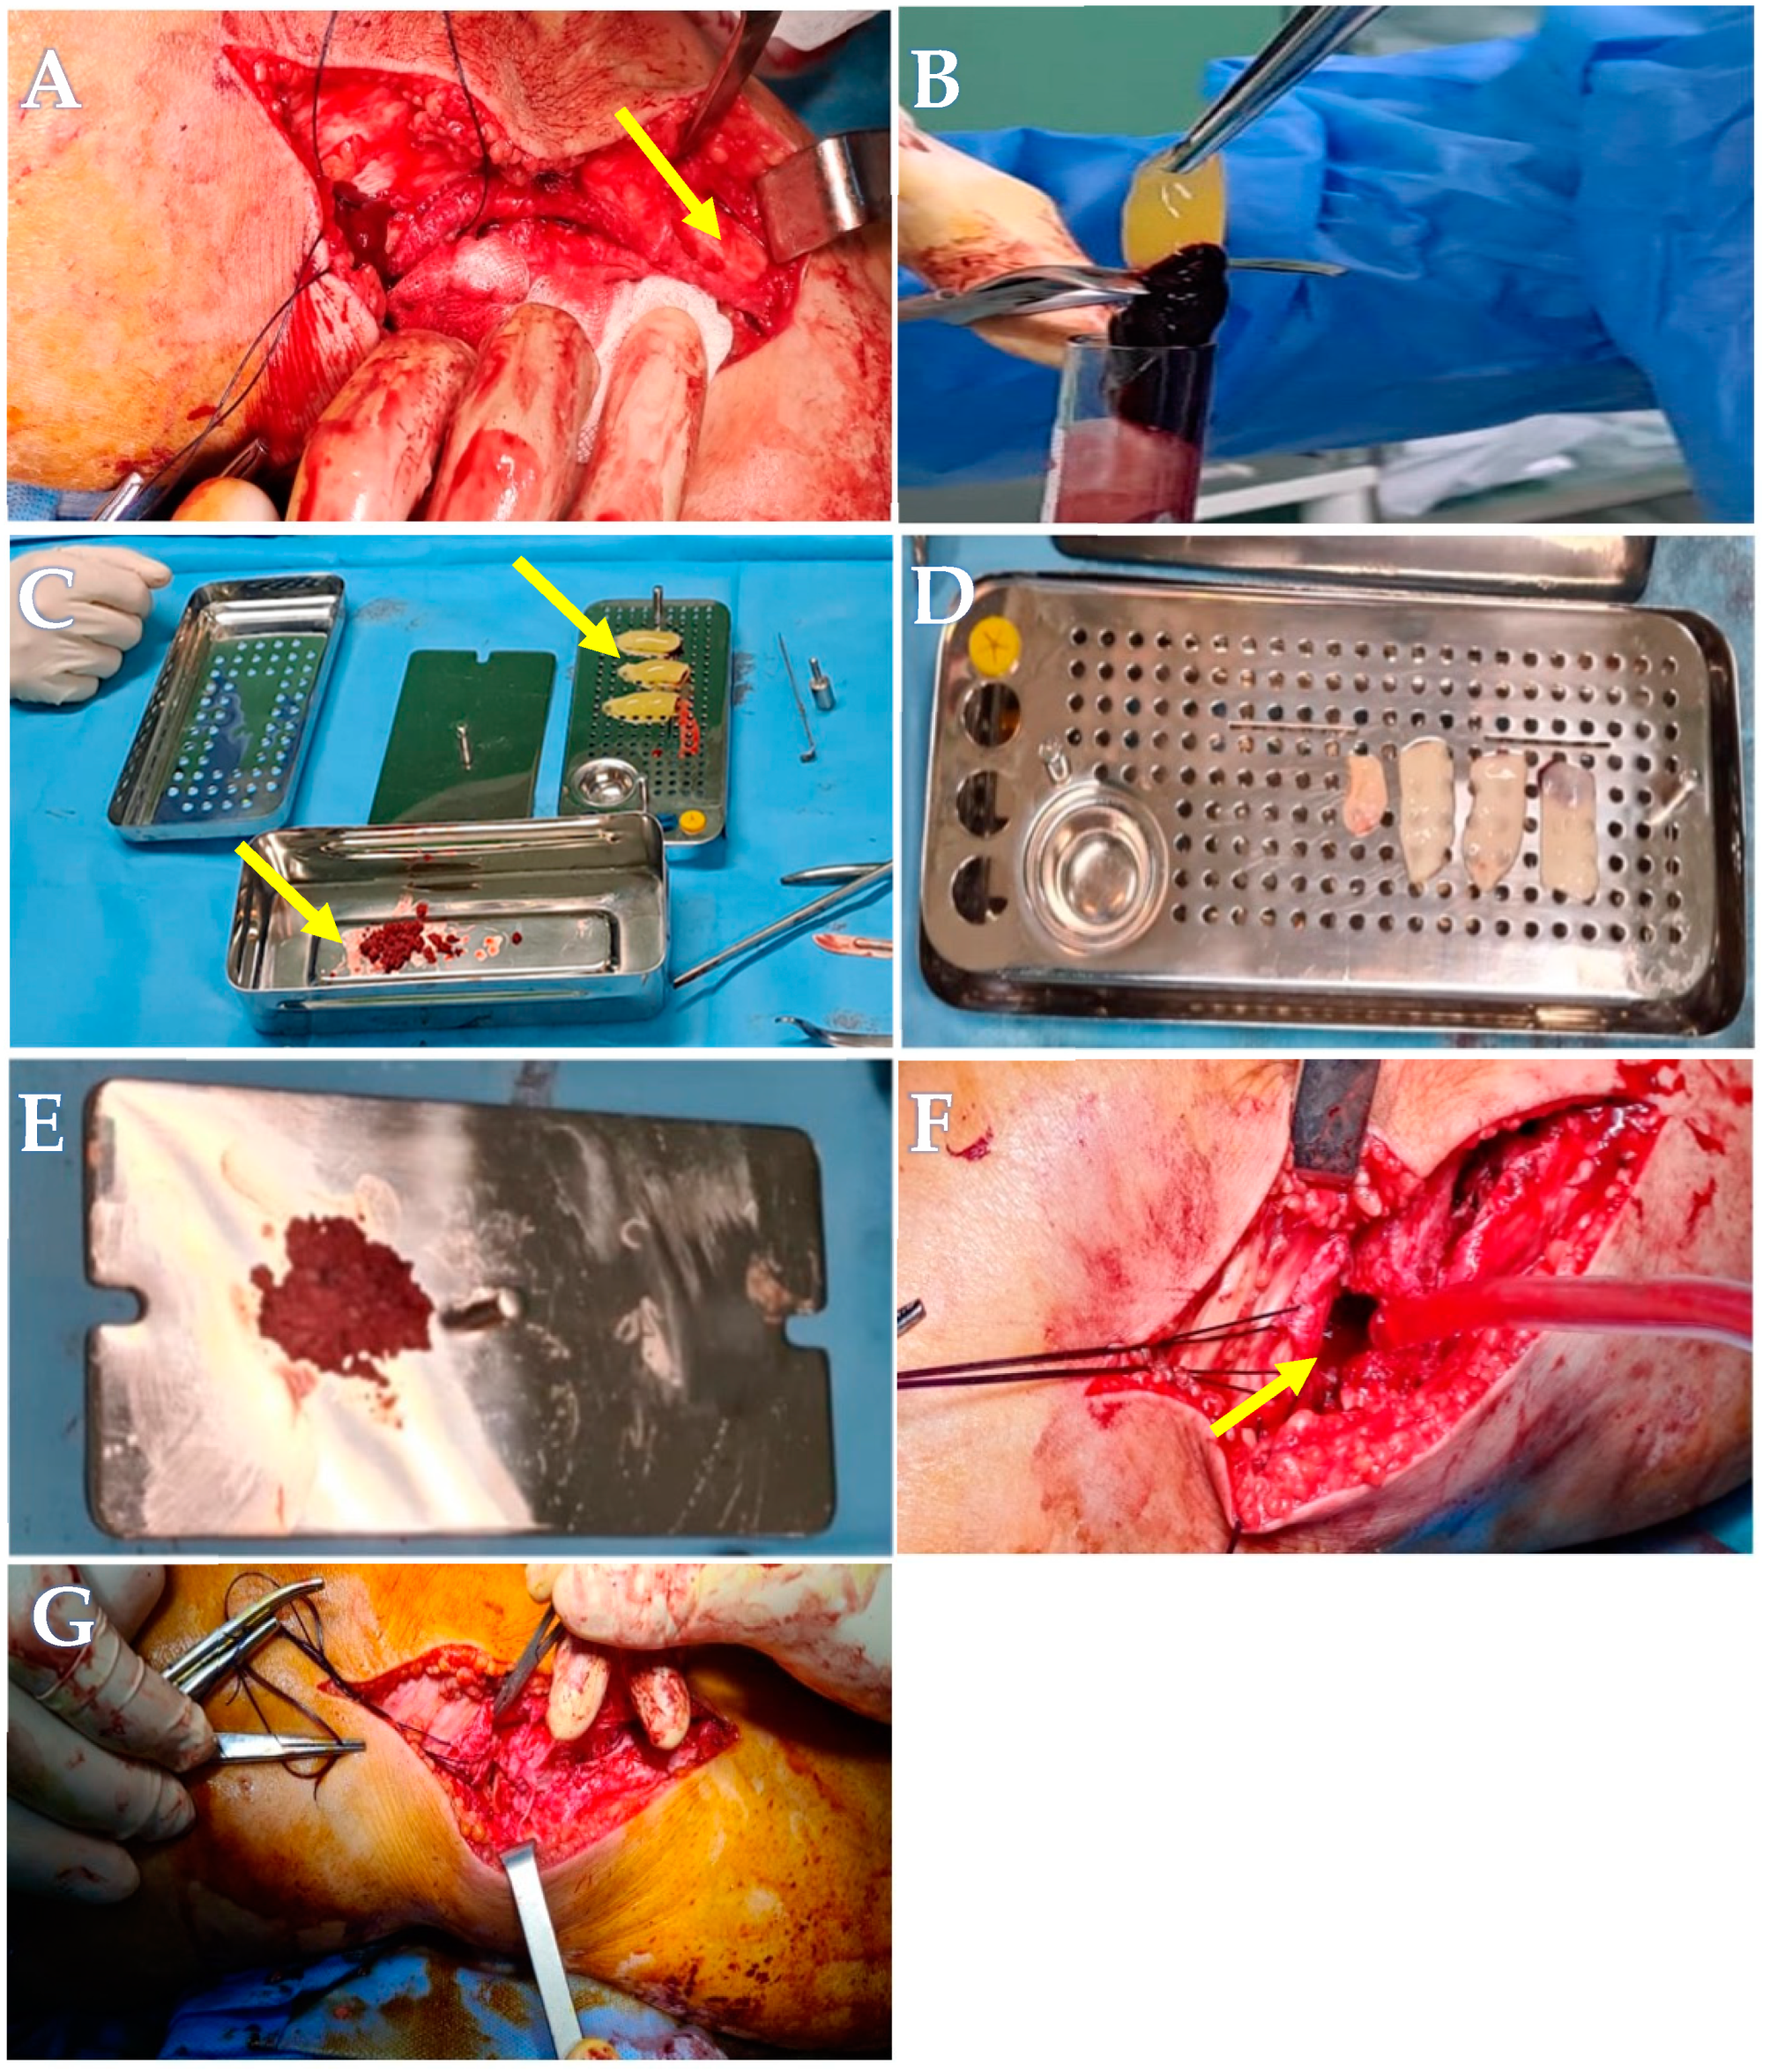

2. Clinical Case Presentation

2.1. Advanced Platelets Rich Fibrin (A-PRF) Membrane and Sticky Bone Preparation